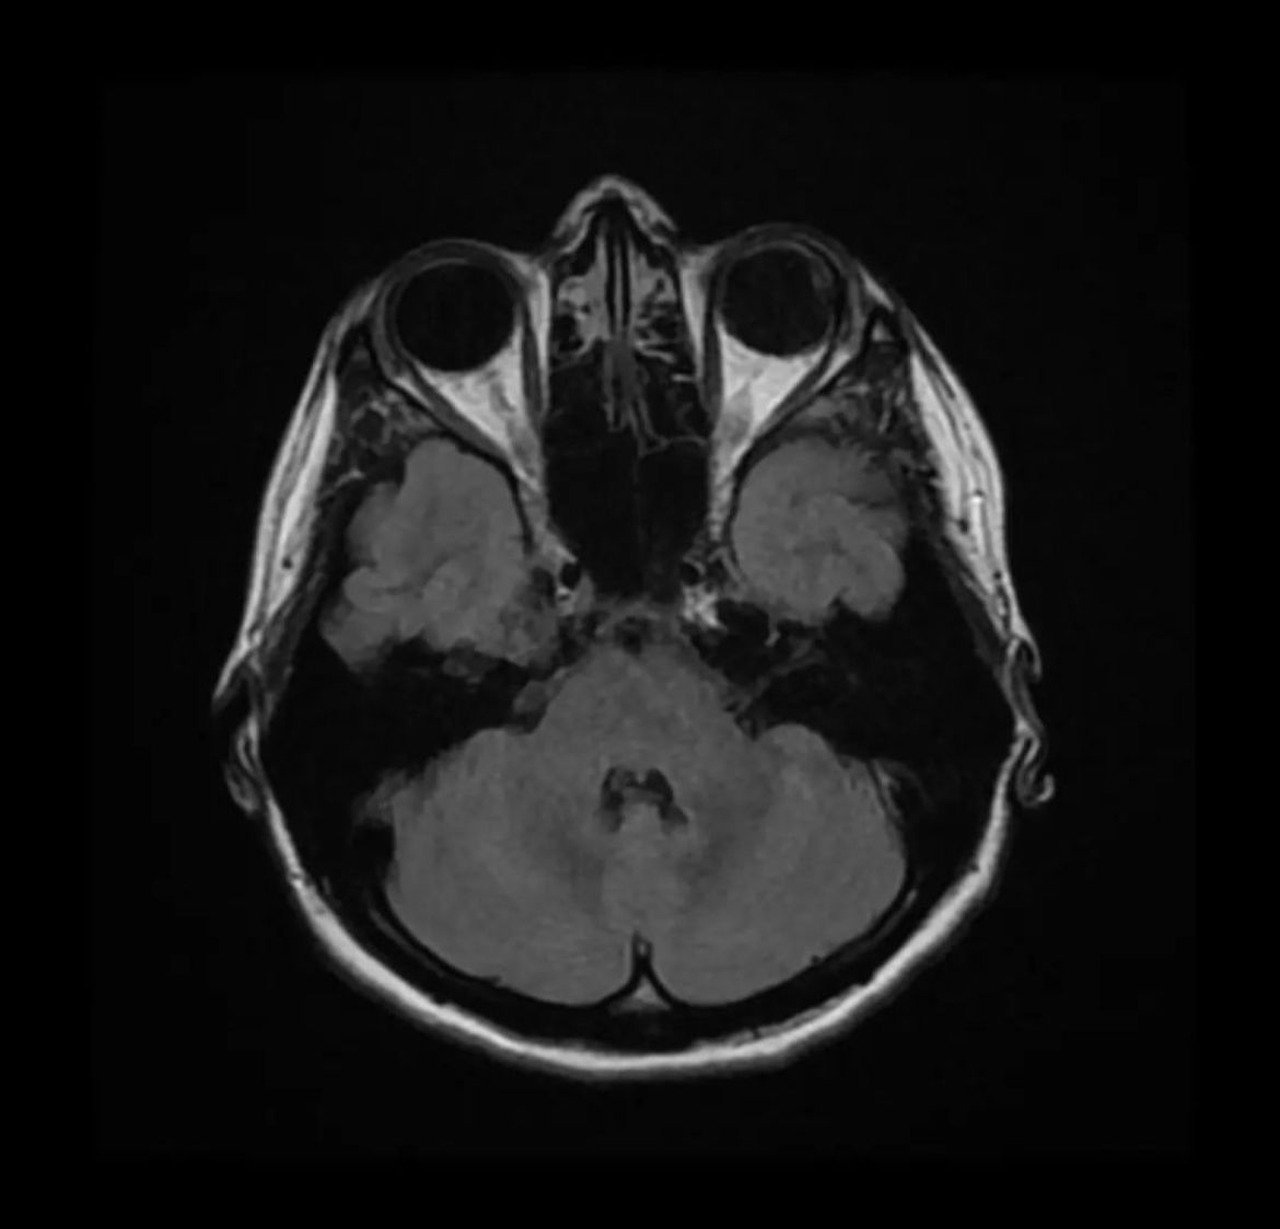

O melanoma ocular é um câncer nos melanócitos, células que dão cor aos olhos. É raro, mas é o tipo mais comum em adultos, especialmente a partir dos 45 anos. Foto: Freepik -